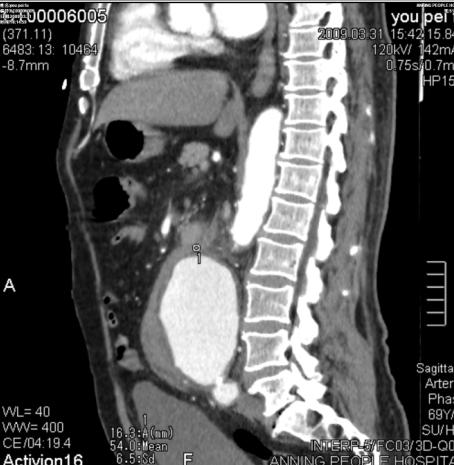

增强后:腹主动脉下段至左右髂总动脉上端明显扩张,最宽处约6.8cm,上下径约为13cm,成瘤样改变,边界清楚,形态规整。

1.腹主动脉瘤。(腹主动脉下段至左右髂总动脉上端)

3.右肾周及腹主动脉周围,中上腹腔见条带状及片状稍低密度影(多考虑腹腔包裹性积液,请结合临床病史。

我(ˇˍˇ) 想~问一下,你是用什么机型作的。很不错。